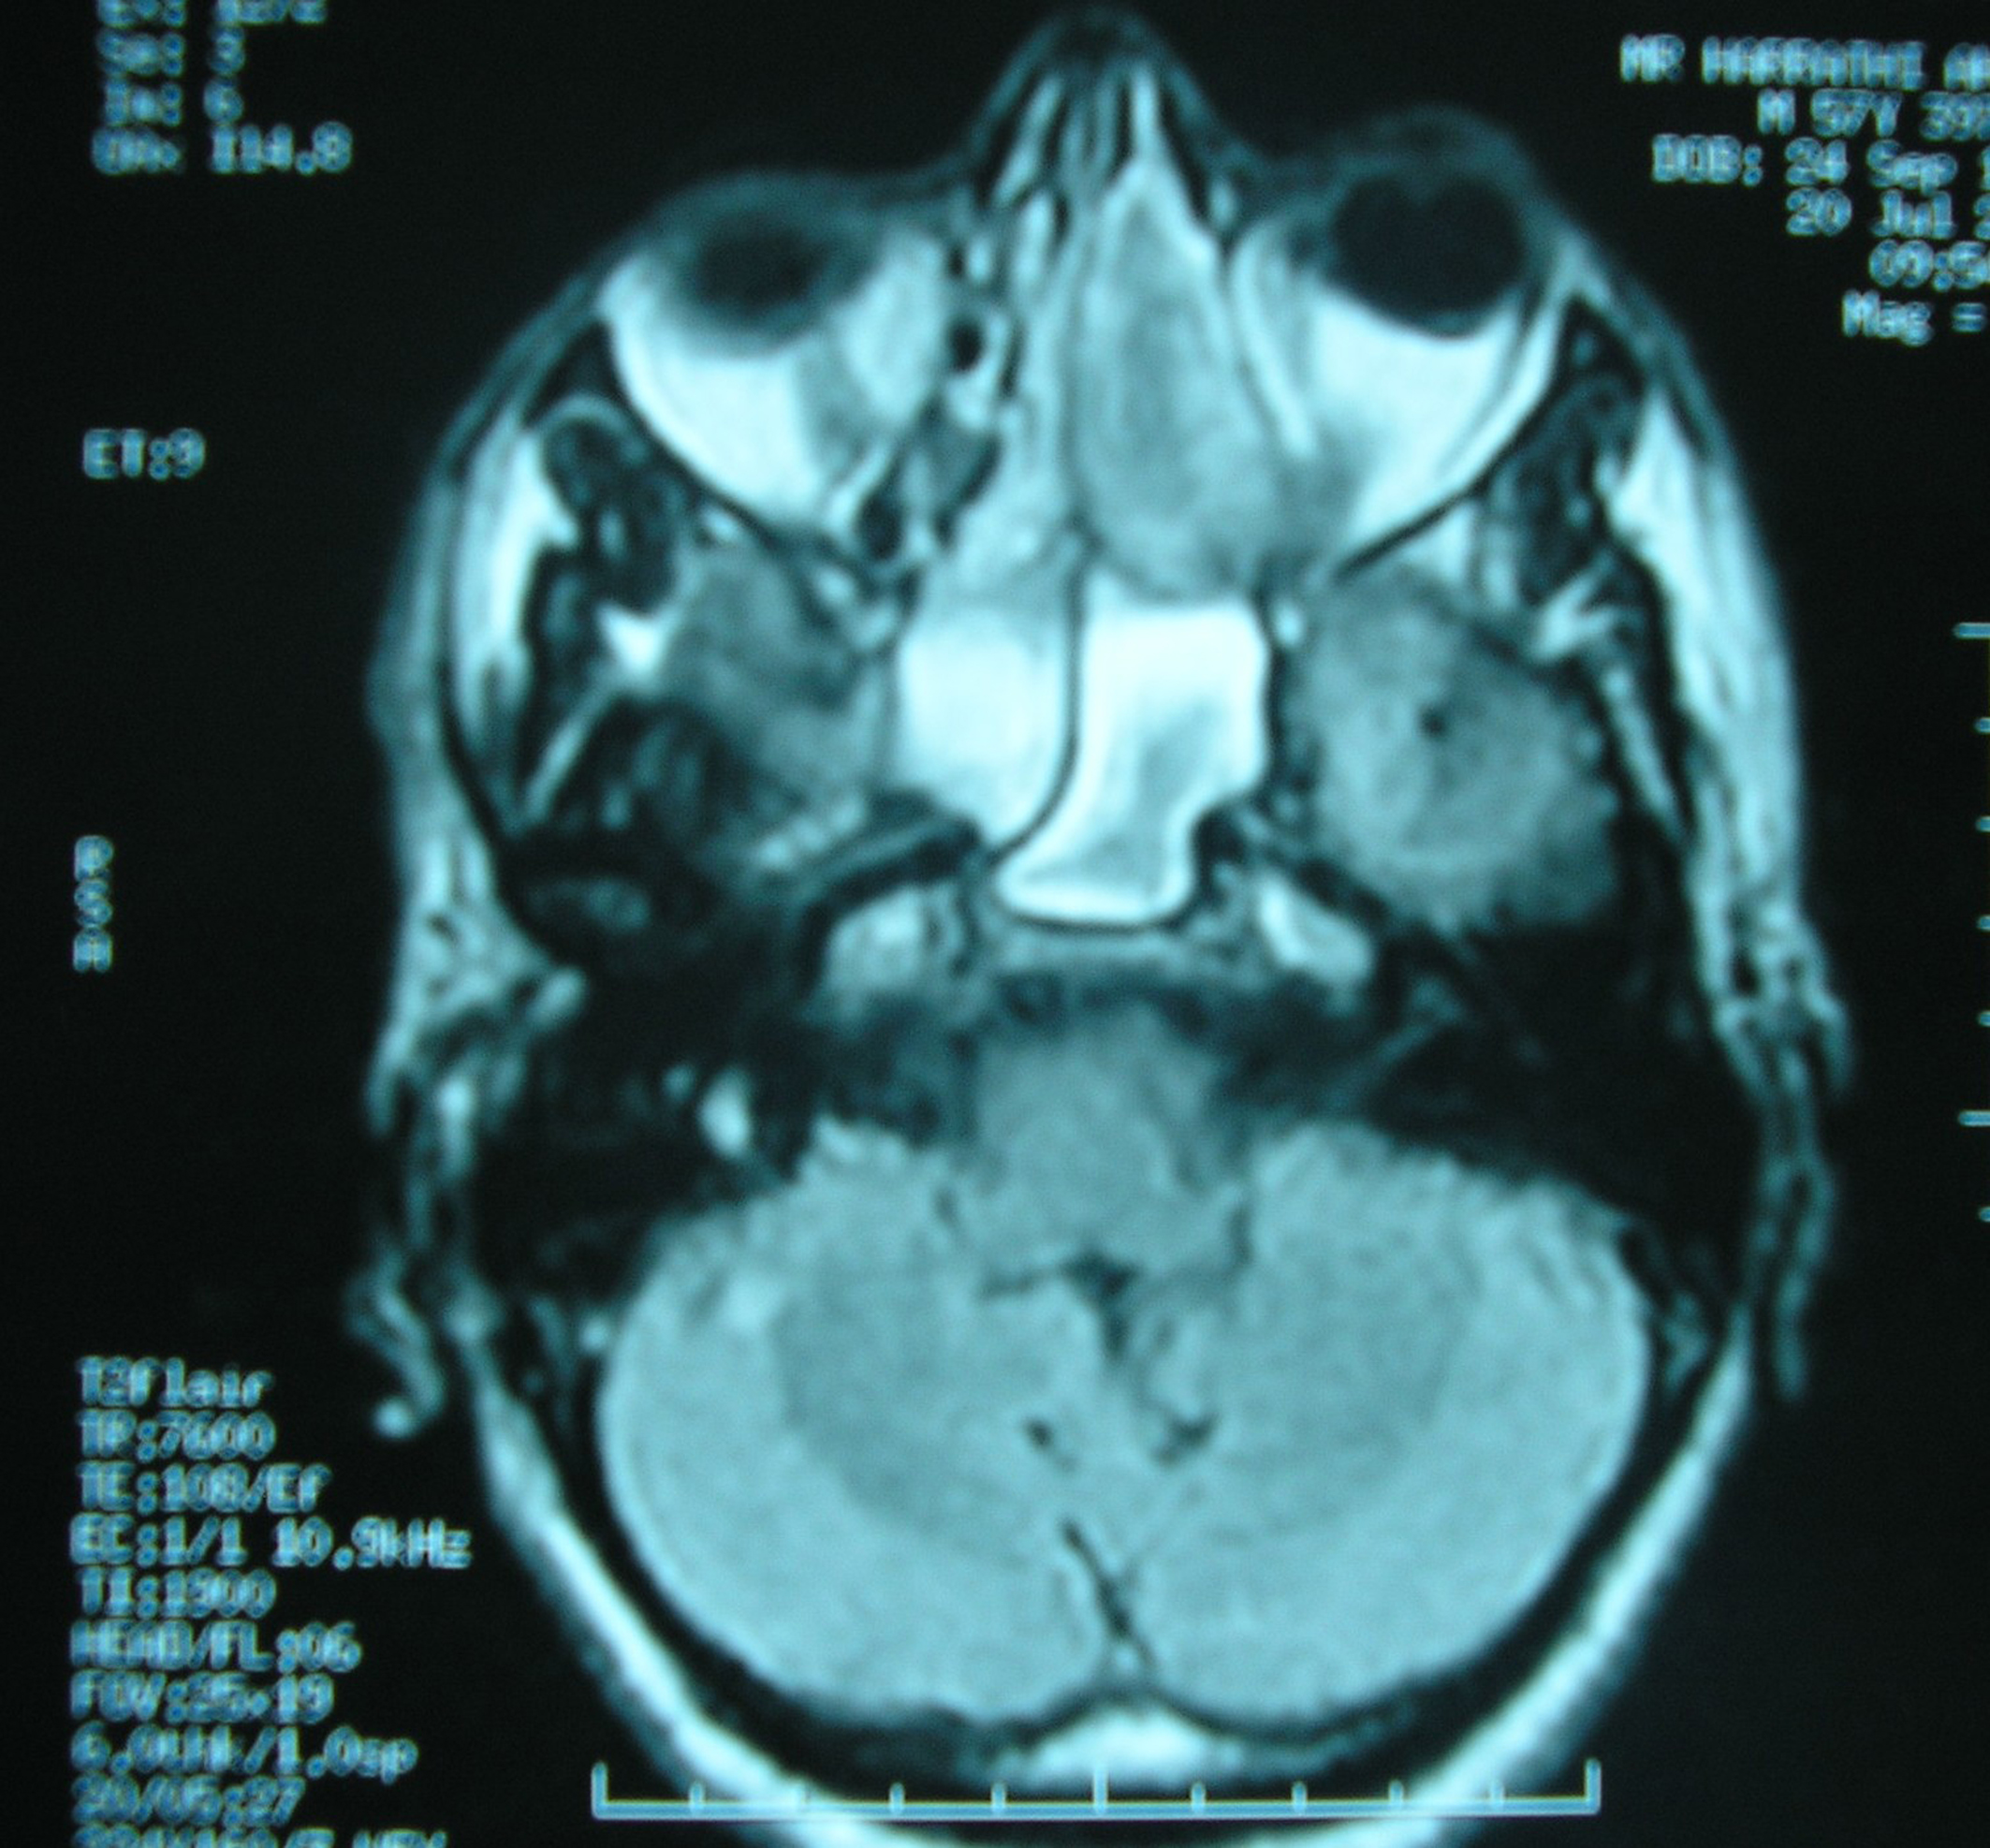

A 58-year-old Tunisian man with no medical history presented with a two months' history of left nasal obstruction and one episode of epistaxis. Nasal endoscopy revealed a smooth reddish polypoid mass of the nasal septum. The mass bled easily whenever palpated by the instrument. There was no evidence of lymph node metastasis. Magnetic resonance imaging (MRI) showed a 30 x 50 mm left nasal cavity tumor with erosion of the orbit (Fig. 1). The tumor was found to originate from the nasal septum. Histological examination of the biopsy demonstrated a tumor proliferation that was made of irregular sheets, islands and single neoplastic cells richly infiltrated by lymphocytes and plasma cells. Epithelial component consisted of large cells with indistinct cell borders resulting in syncitial appearance (Fig. 2), vesicular nuclei and moderate mitotic activity (Fig. 3). Necrosis and keratinization were absent. Immunohistochemically, most of tumor cells were positive for cytokeratin and epithelial membrane antigen (EMA) (Fig. 4). The surrounding cellular infiltrate was a mixture of CD20 and CD3 positive B and T lymphocytes. Immunohistochemical expression of EBV latent membrane protein 1 (LMP1) and in situ hybridization to EBV encoded RNA were positive. The diagnosis of primary LEC NC EBV positive was performed after excluding metastatic nasopharyngeal undifferentiated carcinoma of the nasal cavity by random biopsies from the nasopharyngeal mucosa. The tumor was classified T4N0M0. Systemic chemotherapy was started and consisted in intravenous Adriamycin and Cisplatin. Radiotherapy was done based on 72 Gy in the tumor and 52.2 Gy in the bilateral cervical lymph node region: 1.8 Gy/day, 5 days per week. The patient remains alive and disease free 12 months after treatment.

![]() Click for large image | Figure 1. MRI of nose and paranasal sinuses: nasal cavity tumor with erosion of the left orbit. |